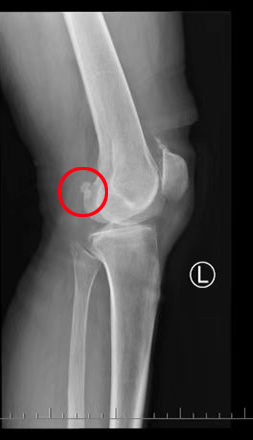

近日,76岁的果奶奶因饱受膝关节疼痛和活动受限的困扰来到首都医科大学附属北京潞河医院骨中心求医,主诉“左膝关节疼痛伴活动受限一个月”。骨中心主任刘亮在检查过程中发现果奶奶主要的问题在于膝关节游离体造成了关节的绞索与疼痛。但老太太因为患有严重的先天性心脏病,这无疑增加了治疗的难度和风险。面对这种复杂情况,骨中心与心脏中心通力合作,最终通过实施缜密的治疗方案,成功解决了老太太的膝关节问题,帮助她重拾起生活的希望。

果奶奶的膝关节因游离体的存在而产生剧烈疼痛,活动几乎受到完全限制,日常生活质量大大下降,甚至连简单的走路、上下楼都变得十分困难。更为糟糕的是果奶奶的心脏健康问题也同样严峻,严重的先心病使得任何手术都面临极高的麻醉风险。经过心脏中心心内科和心外科团队的仔细评估,建议果奶奶需要进一步心脏功能检查评估。虽然果奶奶对膝关节手术有强烈的需求,但她的心脏问题始终是手术能否顺利进行的最大障碍。

在了解了果奶奶的情况后,刘亮主任主动担当起了治疗重任。作为一位经验丰富的骨科专家,刘主任深知膝关节问题对患者生活质量的重要性,同时也充分考虑到高龄和心脏病因素,精心制定了个性化的治疗方案,决定采取局部浸润麻醉,这种方法能在确保患者安全的前提下最大限度减少麻醉风险,但是对术者却提出了更高的要求。刘主任运用膝关节镜技术,顺利地对果奶奶的膝关节进行了探查清理,并成功取出了游离体。整个手术过程非常顺利,术中出血仅为10毫升,手术时间也仅用了28分钟。

术后第一天,果奶奶顺利拔除引流管,X光复查后确认膝关节问题得到有效解决。果奶奶惊讶于膝关节症状的改善,她笑着说:“现在膝关节可以伸直,打弯也没有问题了,感觉自己年轻了不少!”在潞河医院的精心治疗和关怀下,果奶奶不仅膝关节恢复了健康,心脏问题也正在得到有效控制,重拾起生活的希望与信心。